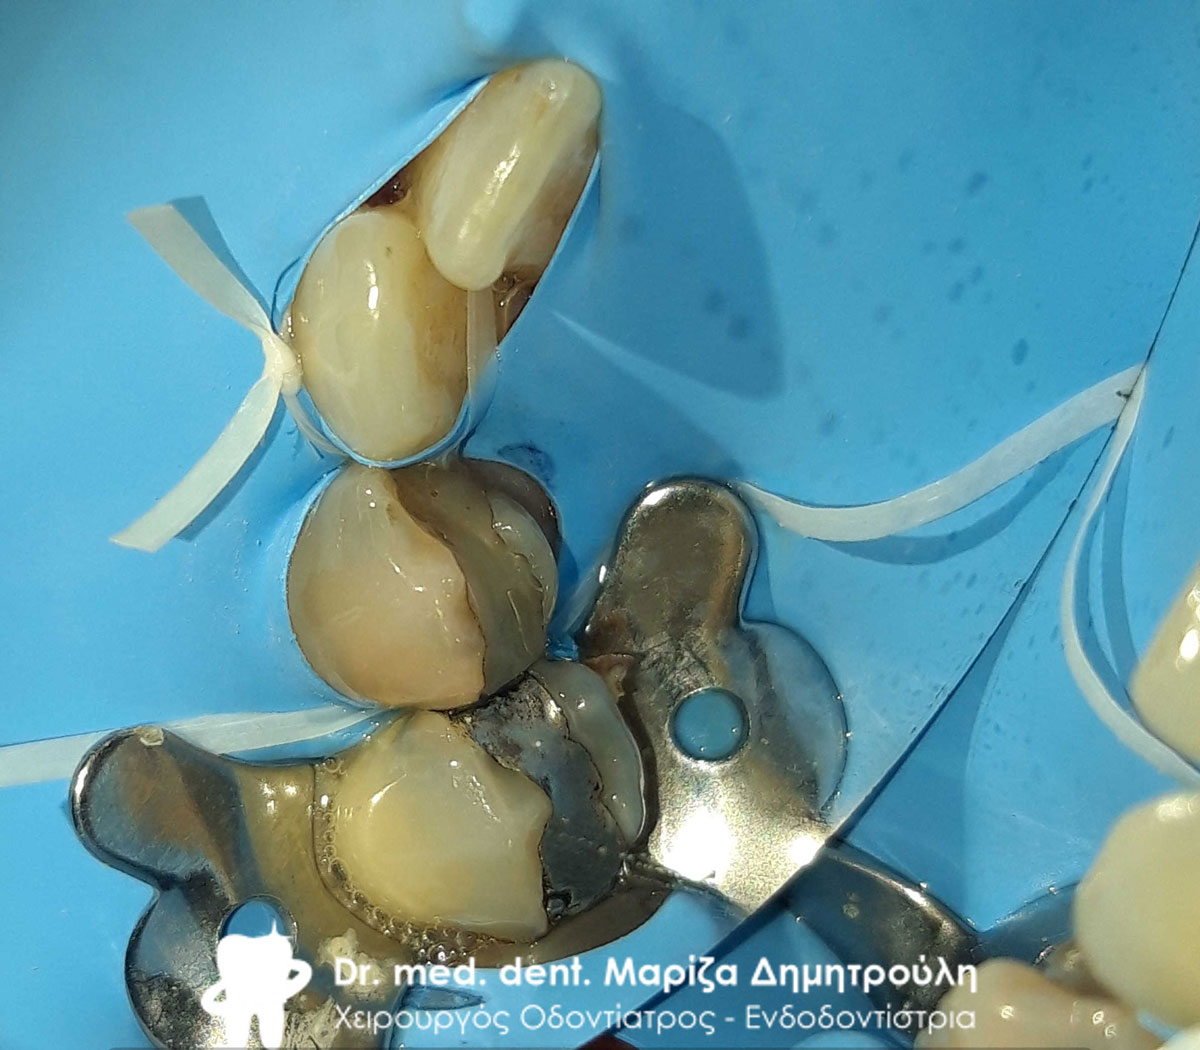

Κολοβώματα δοντιών μετά την ανασύσταση των εναπομείνατων ριζών με άξονες υαλονημάτων

Κολοβώματα δοντιών μετά την ανασύσταση των εναπομείνατων ριζών με άξονες υαλονημάτων

Απονεύρωση του πρώτου προγόμφιου με τη χρήση ελαστικού απομονωτήρα